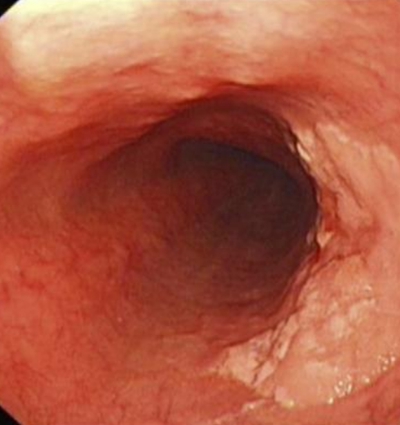

直腸癌圖片